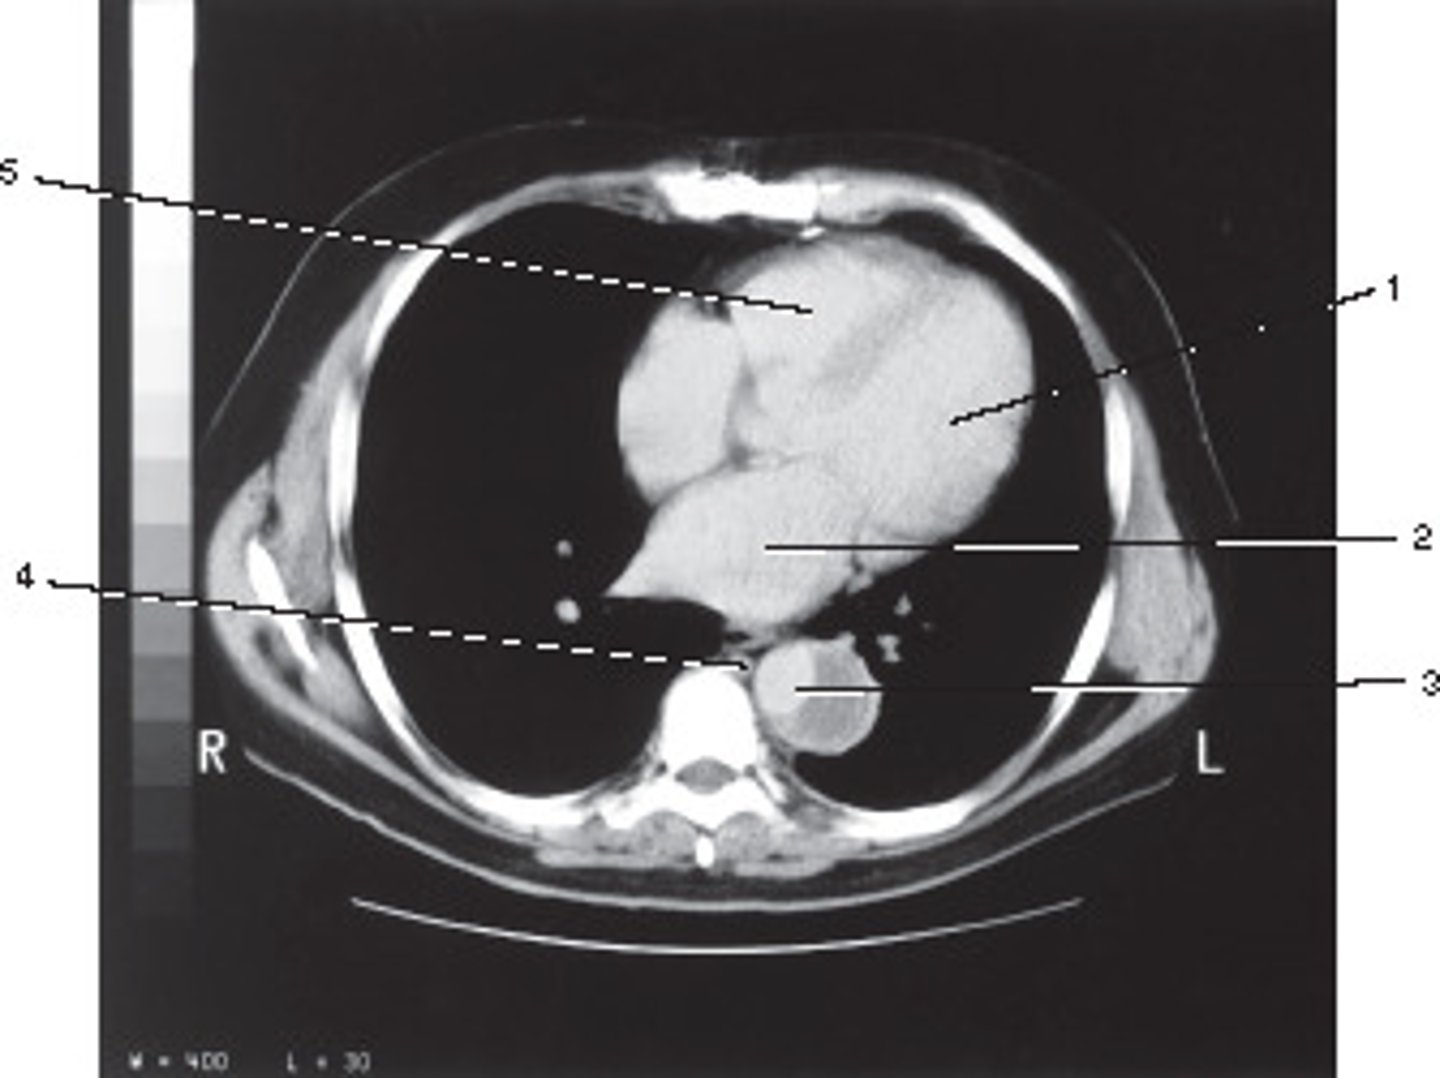

Descending Aorta

Number 1 corresponds to which of the following?

<p>Number 1 corresponds to which of the following?</p>

IV only

On the basis of the appearance of this image, what contast media was utilized?

<p>On the basis of the appearance of this image, what contast media was utilized?</p>

Scapula

Number 4 corresponds to which of the following?

<p>Number 4 corresponds to which of the following?</p>